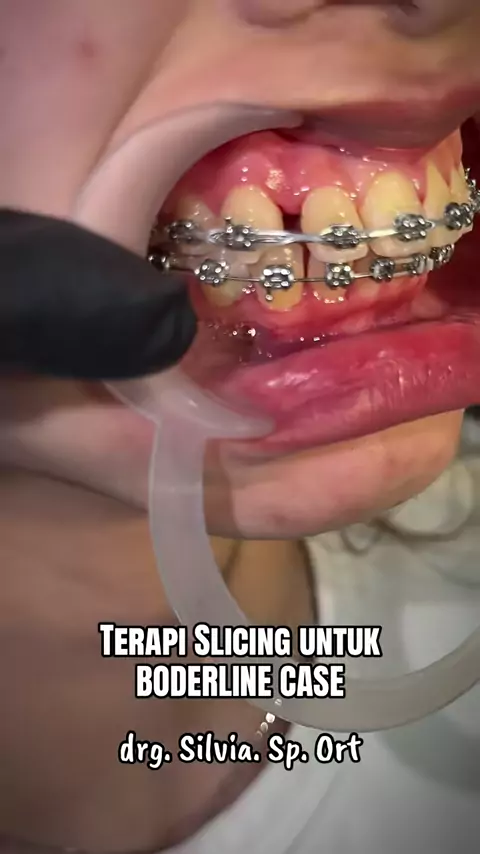

The Oclussion Kunci gigitan, kasus boderline, plek ketika digigit dan ditutup tidak ada cekah atas bawah kecuali sisa ruang sedikit untuk retraksi anterior. good night drg. Silvia. Sp. Ort #behelgigi #behelstory #orthodontist #surabaya #